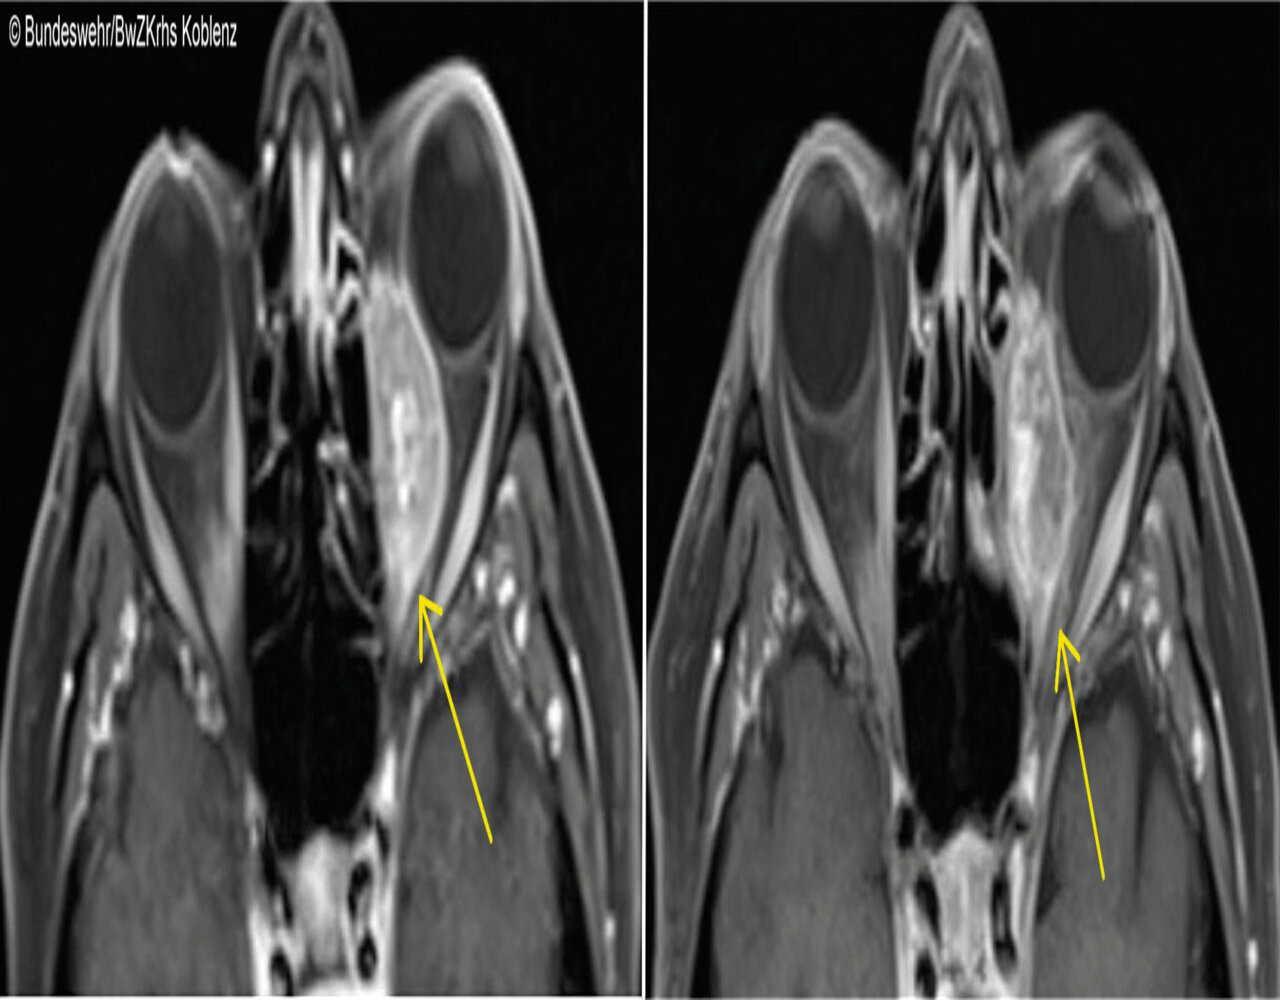

Binnen zwei Wochen entwickelte eine 71-Jährige einen Exophthalmus links mit Lateralverlagerung des Augapfels und Epiphora, begleitet von retrobulbären Schmerzen und einem Druckgefühl. 2018 war bei der Frau ein duktales Mammakarzinom diagnostiziert und mittels Teilablatio sowie adjuvanter Radiochemotherapie behandelt worden. In der Schnittbildgebung stellte sich nun eine 33 x 17 x 19 mm große Raumforderung medial der linken Orbita dar, die stark Kontrastmittel aufnahm (s. Abb. 1). Weitere sus­pekte Befunde sah man im Achsenskelett sowie in axillären, mediastinalen und retroperitonealen Lymphknoten.

Die Ärzte entschlossen sich zunächst zu einer Biopsie, die man in der HNO-Klinik endonasal endoskopisch durchführte. Histologisch ließ sich der Verdacht auf Metastasen des Mammakarzinoms verifizieren. Die Patientin erhielt eine onkologische Weiterbehandlung, darunter verkleinerte sich die Orbitaabsiedlung innerhalb von zwei Monaten auf ein Drittel der ursprünglichen Größe.